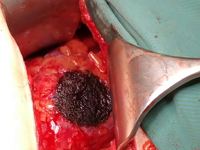

Application of water jet technology and argon plasma coagulation in nephron-sparing surgery for a kidney tumour – a case report.

SurgeryOwing to the ever increasing role of medical imaging (e.g. ultrasonography, computed tomography or magnetic resonance imaging), the number of incidentally detected kidney tumours is growing as well. These tumours are usually small renal masses (SRMs) at early advancement stages (1). According to the guidelines of the European Society of Urology, kidney tumours at early stages (T1) should be treated with nephron-sparing surgery (NSS). In the long term, this type of treatment allows renal function preservation, decreases overall mortality and reduces the incidence of cardiovascular events (2). The main goals of NSS are tumour removal with negative surgical margins and preservation of the best possible function of the remaining renal parenchyma with minimised risk of adverse events. The progress of medical technologies renders surgical procedures more and more effective.